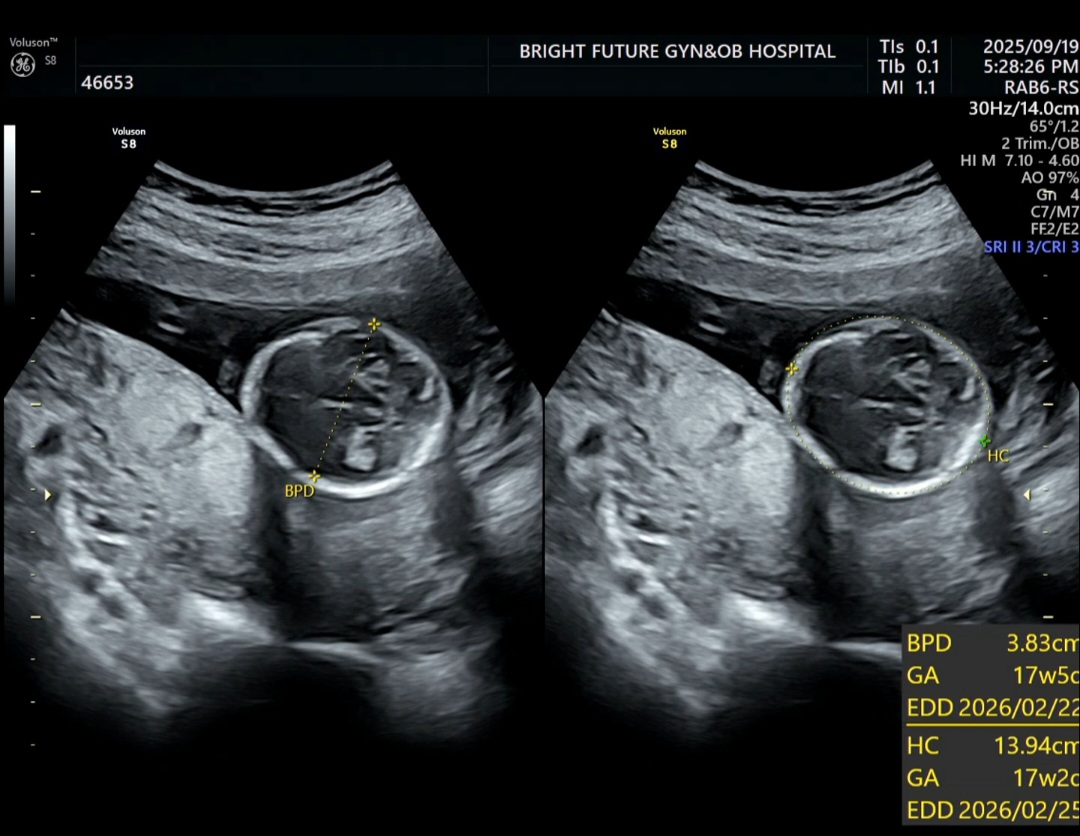

16주 3일차 진료 : 신경관결손 검사

1차 기형아 검사 이후로 2차 기형아 검사를 위해 4주 만에 다시 병원을 찾았다.

나는 1차에서 니프티 검사까지 했기때문에 추가로 신경관결손 여부를 확인하는 검사만 진행됐다.

초음파로 척추와 두개골을 확인하고, AFP(알파피토프로테인) 혈액검사 수치를 통해 이상 여부를 살핀다.

4주만에 만난 꿀떡이는 174g으로 폭풍 성장해 있었다.

심장도 159bpm 으로 정상범위에서 잘 뛰고 있었다.

초음파에서 척추도 선명하게 보였고, 구멍 같은 이상 소견은 없었다.

엄마, 아빠가 머리가 작은편이 아니라 매번 머리 직경을 잴 때 마다 불안불안하다.

역시! 주수보다 1주일 넘게 큰 머리..

출산때까지 머리직경 10cm 가 넘으면 머리가 크다고 본다고 했다.